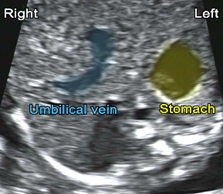

- Confirm that both the stomach and heart are on the left side

Obtain the 4-chamber view and maintaining a transverse section of the fetal trunk, angle or slide the transducer downwards to the abdomen, in order to image the stomach and situs

Abdominal situs